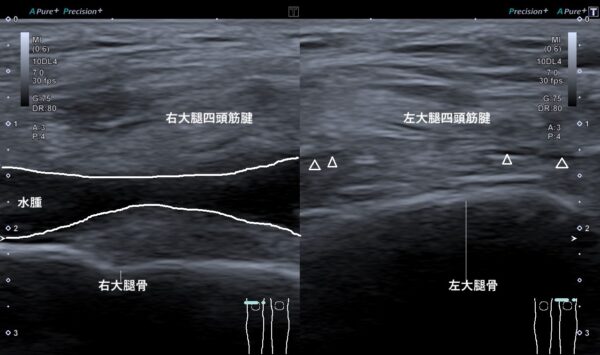

右膝に水(関節液)が溜まっていると推察し、超音波画像検査を行ったところ、やはり関節液が過剰に溜まっていました(画像、白線で囲んだ黒いエリア。矢頭の先のわずかな黒い箇所が関節液の正常な量)。

関節液が過剰にたまったのは、膝蓋骨を階段にぶつけた際に軟骨が損傷して炎症(軟骨組織を修復する反応)を引き起こし、関節液を分泌する滑膜が刺激されたことが原因と考えられます。